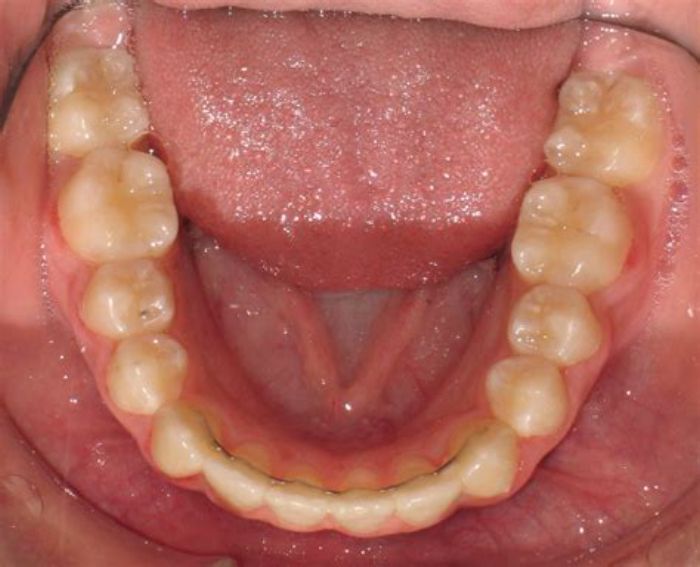

Festsitzender Retainer: Ein dünner, individuell angepasster Draht, der dauerhaft an der Innenseite der Frontzähne – meist im Unterkiefer – befestigt wird. Er ist von außen nicht sichtbar und besonders geeignet für die langfristige Stabilisierung der Zähne. Der Vorteil: Er wirkt rund um die Uhr, ohne dass Patient:innen daran denken müssen.